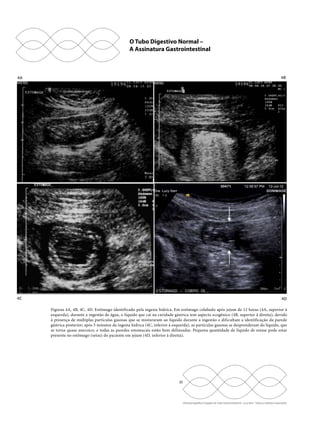

Figuras 3E, 3F. US de antro gástrico, piloro e bulbo duodenal normais. A porção do antro (3E, à esquerda), mais plana (setas retas maiores),

está em contato com a cabeça do pâncreas posteriormente e conecta-se diretamente ao duodeno, que exibe sua bolha na topografia do bulbo

(seta curva), e, entre ambos, está o piloro (setas retas menores). Na outra imagem (3F, à direita), um estreitamento é visualizado na saída do

estômago, na projeção do piloro (setas).

Figuras 3G, 3H. US de estômago normal. As dobras do corpo e fundo gástrico não são habitualmente identificáveis, mas podem ser vistas

em estômago (setas) distendido por pequena quantidade de líquido na imagem (3G, à esquerda) ou muito colabado pelo jejum prolongado

e com as dobras acentuadas pelo edema (setas) na outra imagem (3H, à direita).

Figuras 4A, 4B, 4C, 4D. Estômago identificado pela ingesta hídrica. Em estômago colabado após jejum de 12 horas (4A, superior à

esquerda), durante a ingestão de água, o líquido que cai na cavidade gástrica tem aspecto ecogênico (4B, superior à direita), devido

à presença de múltiplas partículas gasosas que se misturaram ao líquido durante a ingestão e dificultam a identificação da parede

gástrica posterior; após 5 minutos da ingesta hídrica (4C, inferior à esquerda), as partículas gasosas se desprenderam do líquido, que

se torna quase anecoico, e todas as paredes estomacais estão bem delineadas. Pequena quantidade de líquido de estase pode estar

presente no estômago (setas) do paciente em jejum (4D, inferior à direita).